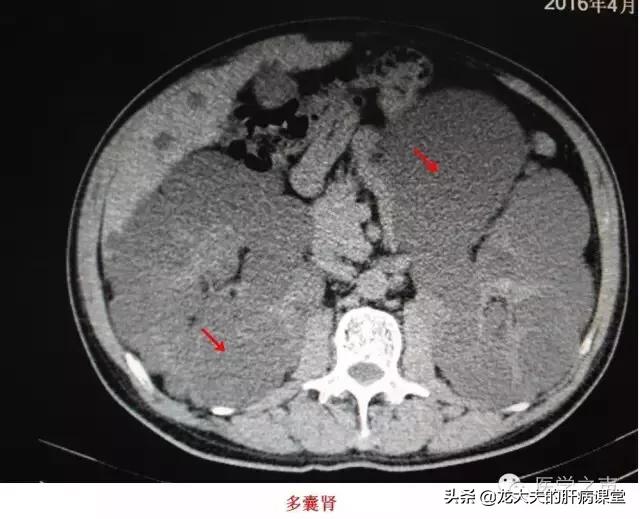

肝嚢胞の大きさに注意を払うだけでなく、同時に出現する多発性嚢胞腎の問題にも特に注意を払う必要があるが、多発性嚢胞腎は病気の進行とともに腎不全を引き起こす可能性があり、より注目される!

多発性肝嚢胞は多発性嚢胞性肝とも呼ばれ、多発性嚢胞性腎を有する患者に多くみられる。 多発性嚢胞性腎を有する患者では、肝嚢胞の発生率は加齢とともに増加するが、これは肝臓の内部構造の発達に関係している。

これらの多発性嚢胞腎患者のうち、30歳未満の患者では、多発性嚢胞肝臓を発症する確率は10〜20%である;一方、60歳以上の患者では、50~70%の確率で多嚢胞性肝臓を発症する。

合併症の危険性:多発性肝嚢胞患者は多発性嚢胞腎を伴うことが多く、統計によると、患者の約1/3~1/2が多発性嚢胞腎を伴っており、多発性嚢胞腎は腎不全につながる可能性があり、致命的な危険性がある。